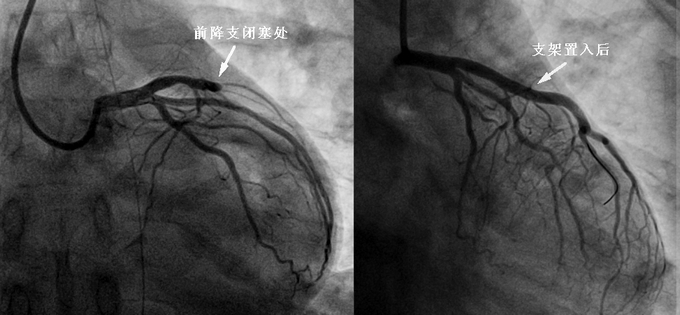

7月15日上午9点40分,一辆120救护车风驰电掣般地驶入我院急诊科,车上抬下来一名男性患者:没有呼吸、没有心跳、瞳孔散大、心电图显示心脏直线,已经没有了生命的迹象,然而120急救医生没有放弃,不间断地为患者实施胸外按压。强烈的责任心使急诊科医护人员也没有放弃一线希望,气管插管、呼吸机辅助呼吸,持续的胸外按压、强心药物的给予。三名医生、三名护士轮流上阵、持续胸外按压,汗水完全浸湿头发,白大衣也像被水洗过了一样。付出终于得到回报,全力抢救近50分钟后患者出现了生命迹象!血压、心率恢复,但仍没有呼吸、处于重度昏迷状态。医疗部统一调度,将患者送入EICU继续抢救。复查患者心电图显示前壁心肌梗死,三根冠状动脉中最大的一根动脉闭塞,请心内科二线会诊后决定立即进行急诊介入手术,在家属的同意下,火速将患者送往导管室。导管室里,闻讯赶来的麻醉科医生熟练的接上了呼吸机,介入相关人员训练有素地进行消毒、铺巾、穿刺、置管,15分钟后打开了危及生命、完全闭塞的最大冠状动脉——前降支,恢复了血流。而后患者被送入ICU病房,在医护人员的精心照料下,患者恢复意识、顺利拔出了气管插管,等待完全康复出院。